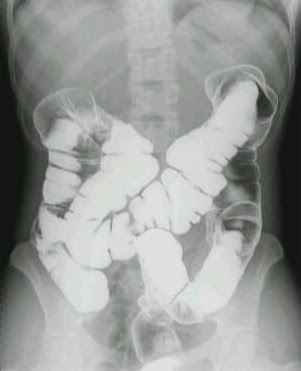

8. Barium Enema.

It is last barium study. It is a radiological contrast medium investigation which demonstrates whole large Bowel from rectum upto the illeo-ceacal junction. Don't confused with reversal order of digestive tract in definition. This exam in perform through rectum by pushing Barium sulphate suspension as contrast medium in it.